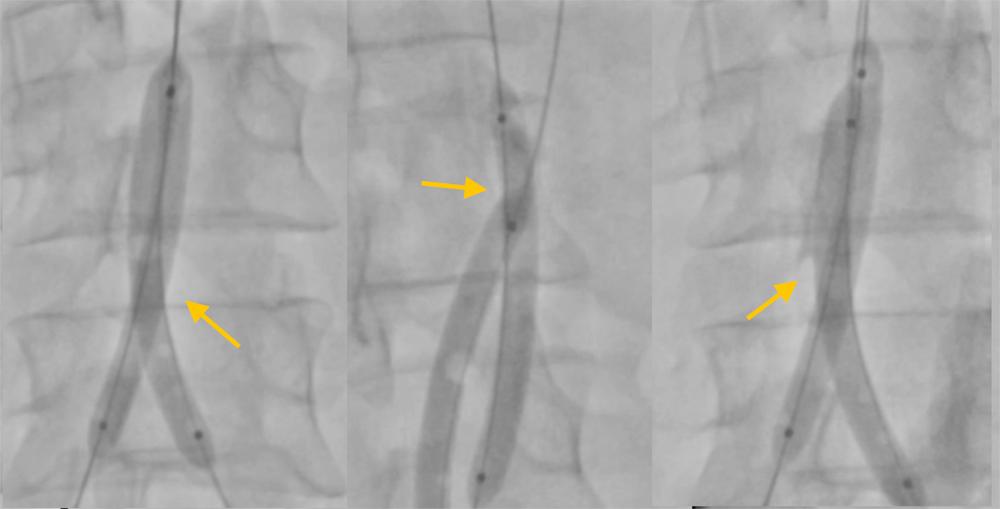

The SMFM size should be selected similar to the methods described. In aortic dissection, visceral branches may arise from the false lumen. In these cases, the operator should use a process known as endovascular scissoring ( Fig. 24.1 ). Two 12×60 mm balloons should be advanced into both the true and false lumens and concomitantly inflated at the level of the aortic bifurcation. These should then be pulled caudally to cut the septum. Alternatively, a 12-French sheath with two superstiff wires, one in each of the true and false lumens, can be used to divide the septum. The ultimate aim of dividing the septum between the true and false lumens is to equalize the pressure between them.

Fig. 24.1, Endovascular Scissoring.